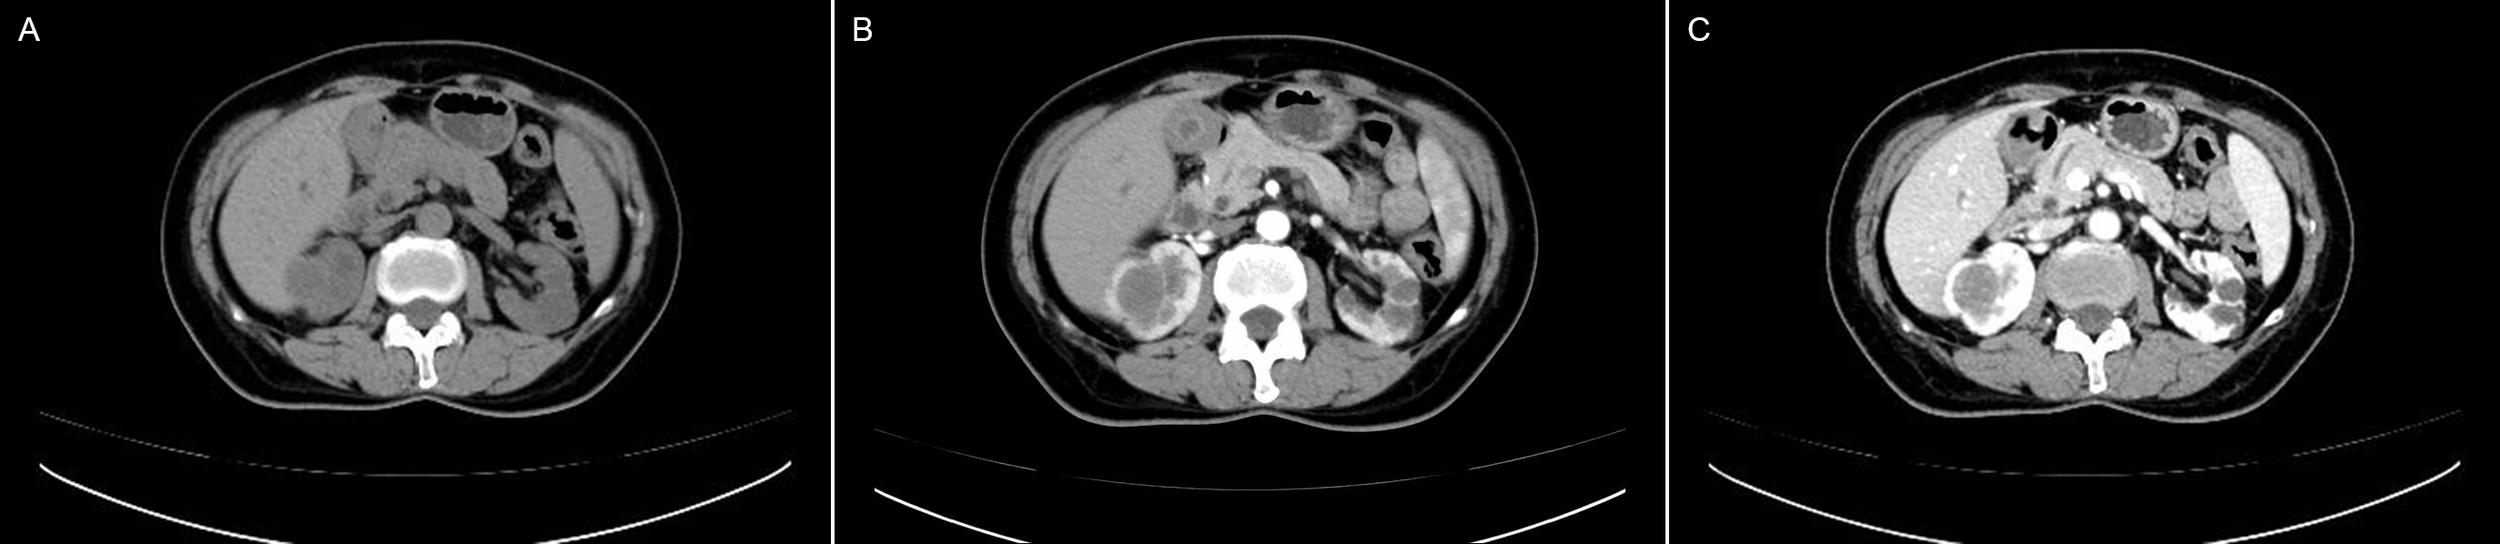

CT features

Eight patients underwent plain CT and CECT. One patient underwent plain CT. All tumors grew expansively with a spherical or ovoid shape on CT images and had well-demarcated margins. Plain CT showed equal or low density. Compared to the normal renal parenchyma in the study, most of tumors (7/9) show homogenous in plain CT. A calcification was observed in only one patient from our series. CECT scanning showed slight heterogeneous enhancement in 6 patients, mild homogeneous enhancement in 2 patients. All lesions exhibited slow and progressive enhancement in the late phases. All lesions showed no hemorrhage, cystic degeneration or necrosis. Figure 2 showed the plain CT and CECT performance of Case 10. All CT results (including plain CT and CECT) of 9 patients were reported malignant renal tumors without further diagnosis of the tumors.

Figure 2

Computed tomography and contrast-enhanced computed tomography images of MTSCC: (A) CT plain scans showed a homogeneous slightly low density mass in the right kidney. Enhanced CT showed homogeneous mild delayed enhancement in arterial (B) and venous phases (C).